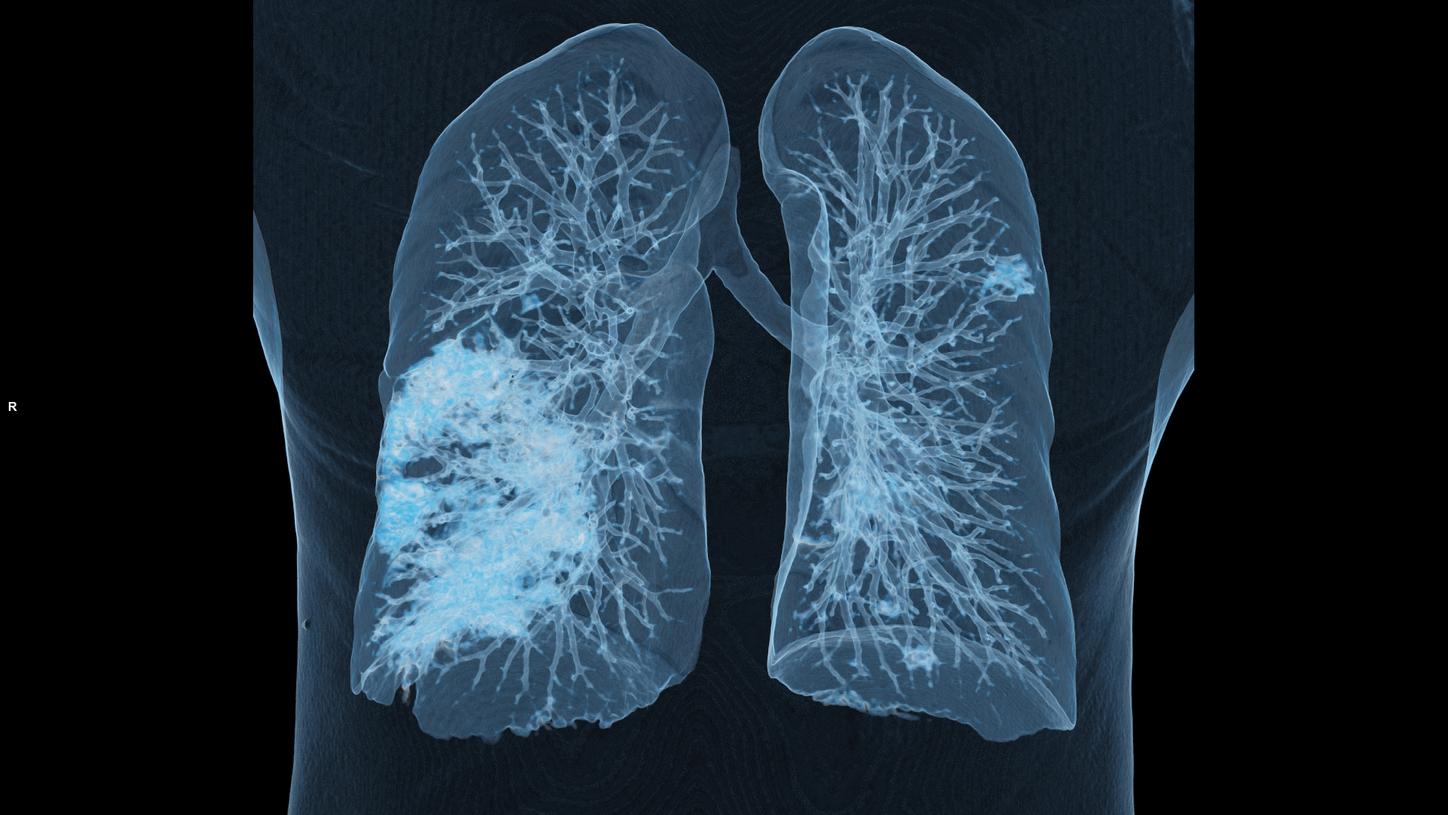

Leading AI scientist Bogdan Georgescu and his team have developed an algorithm that could greatly benefit clinicians in future by helping them to assess COVID-19 severity and progression.

Hot on the trail of COVID-19: Working with collaborators from around the world, a team began developing an algorithm that helps to evaluate changes in lung tissue. Read about how scientists reached a significant milestone during the pandemic.

Solutions that are based on artificial intelligence can ease the workload of radiologists by providing experts with analyses for further assessment. For radiology, this means greater efficiency.